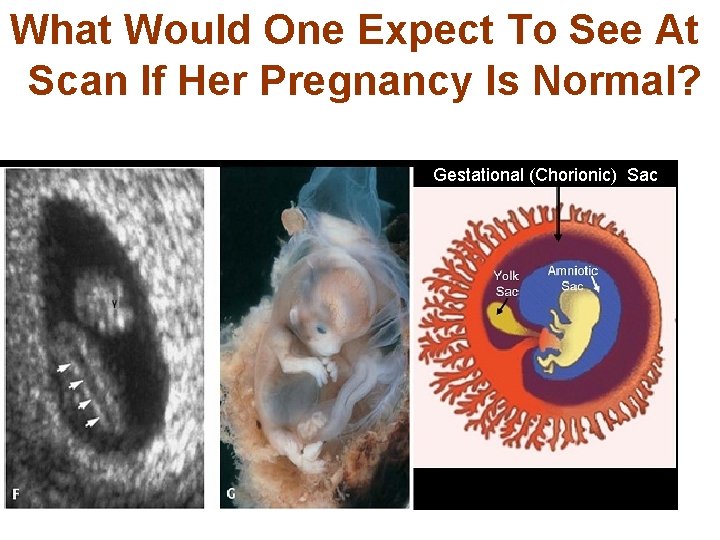

What Would One Expect To See At Scan If Her Pregnancy Is Normal? Gestational (Chorionic) Sac